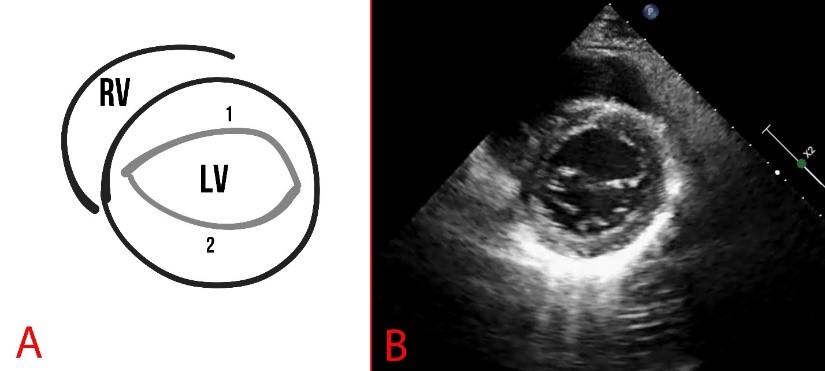

The anterior leaflet of the mitral valve is larger than the posterior mitral leaflet and more mobile. MVP is assessed during systole (at the moment the valves close) and is considered true when a prolapse is registered in two or more views (Figs. 5,6).

Fig. 5. Schematic representation (A) and echocardiography (B) of parasternal short-axis view at the level of the mitral valve. A fibrous annulus of the mitral valve is marked, 1 is the anterior leaflet, and 2 is the posterior leaflet of the mitral valve. RV, right ventricle.

Parasternal short-axis scanning at the level of the mitral valve can reveal pathologies such as splitting of the posterior leaflet into two components, as well as myxomatous degeneration, thickening of the leaflet, convoluted structure, or elongation of the leaflets and chords (Fig. 5).